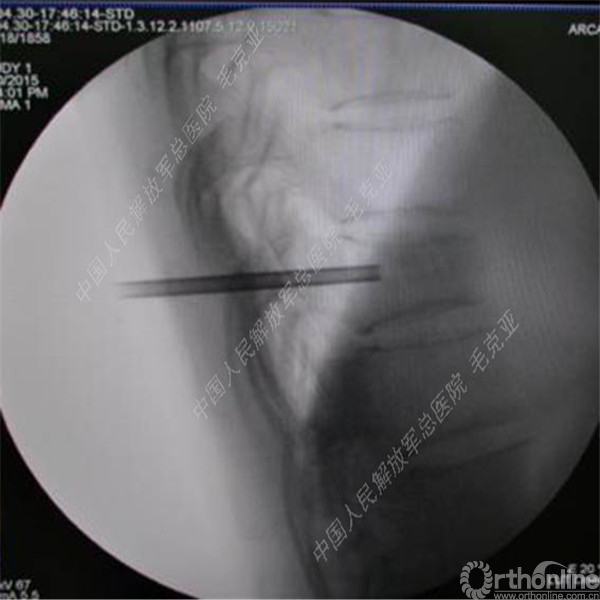

导语:随着社会老龄化的不断加速,骨质疏松性椎体压缩骨折作为一种普遍存在的老年骨科疾病已经成为现今骨科界的一个热点话题。传统的保守疗法治疗效果不佳,而现有的椎体增强技术又具有多种风险和缺陷。针对这种现状,中国人民解放军总医院毛克亚教授提供了一种新的解决方法。